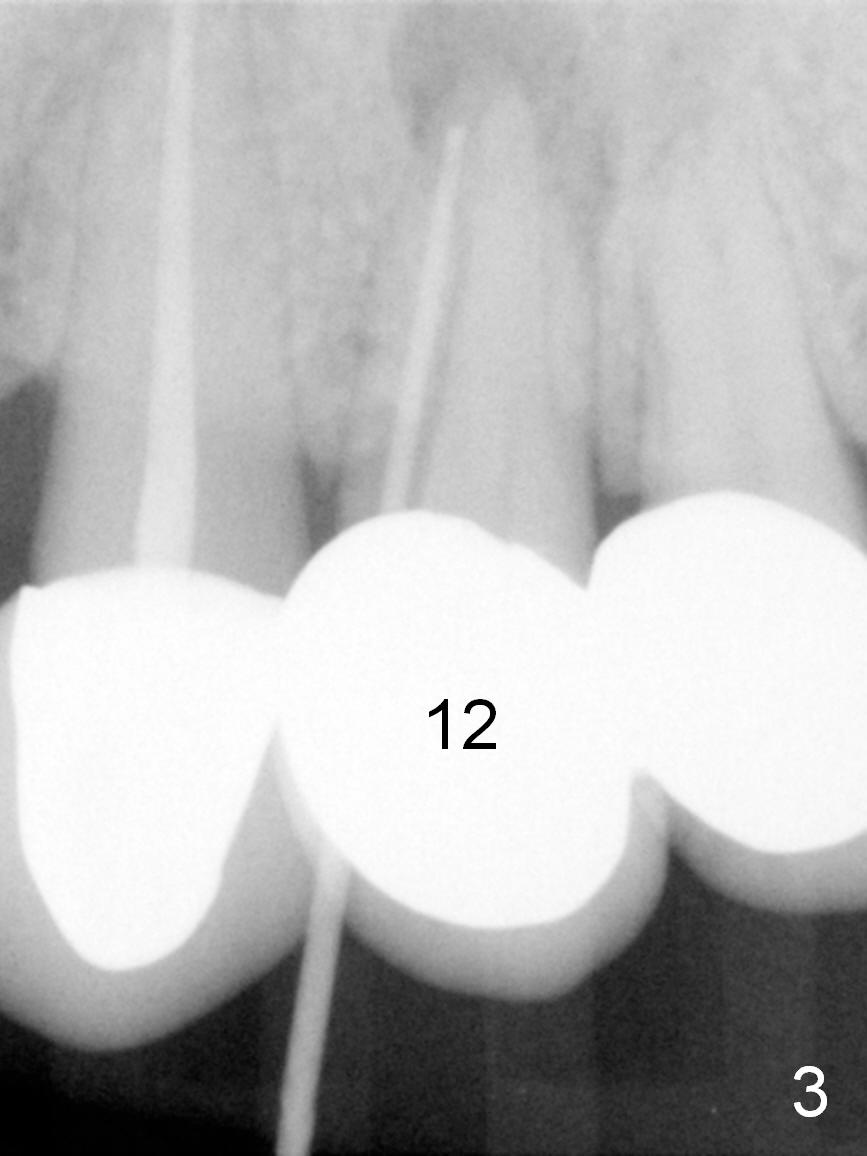

A 43-year-old woman has a persistent, asymptomatic fistula buccal to the tooth #12 (Fig.1,2). Prior to treatment, a #30 gutta percha is inserted into the fistula to confirm diagnosis (Fig.3). Hand files #15 and 20 are inserted to the buccal and lingual canals at 18 mm, respectively (Fig.4). Master cones (30/.04) are inserted buccally and lingually for 18 and 17 mm, respectively (Fig.5). There is minimal paste leakage after finishing RCT (Fig.6). Out of curiosity, the fistula is immediately curetted with removal of 2 small pieces of apparently leaked paste with minimal discomfort (total anesthetic: Xylocaine 34 mg, Epi 17 mcg). The fistula is expected to heal in 2 weeks.